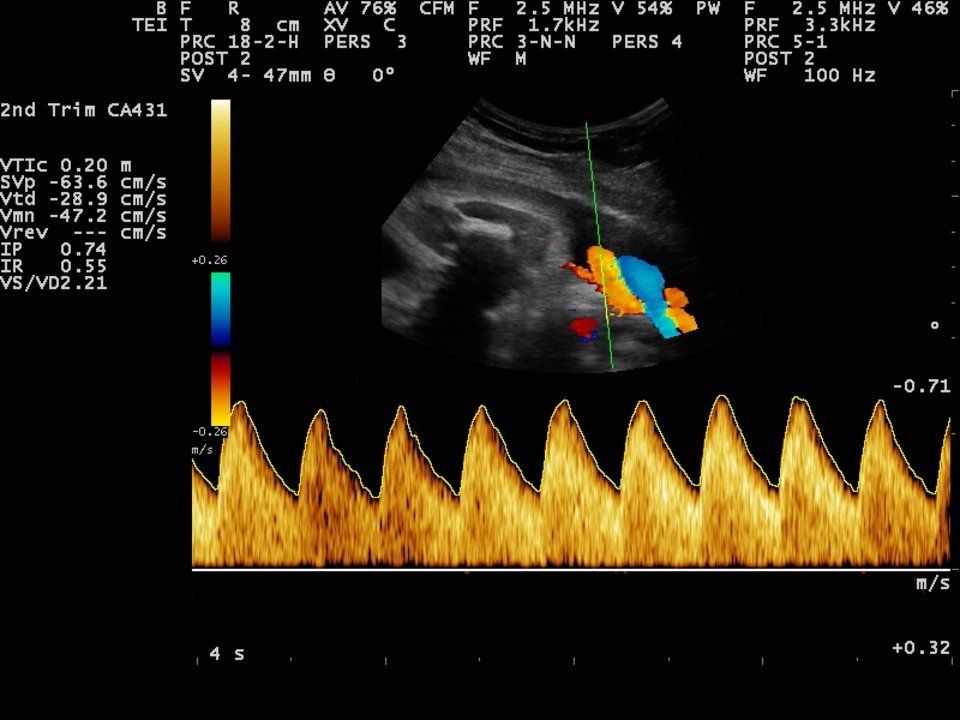

- Medición Doppler de la arteria umbilical.

- Medición Doppler de la arteria cerebral media.